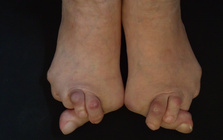

靴の健康被害、外反母趾。

ご相談者の多くの方が

歳を重ねながら足に適切な環境の靴を求める事が出来ず

痛みを増し、変形症状、体を支える事が大変になり

歩行の困難、膝や腰などの痛みの発症に。

外反母趾の問題は痛みだけではありません。